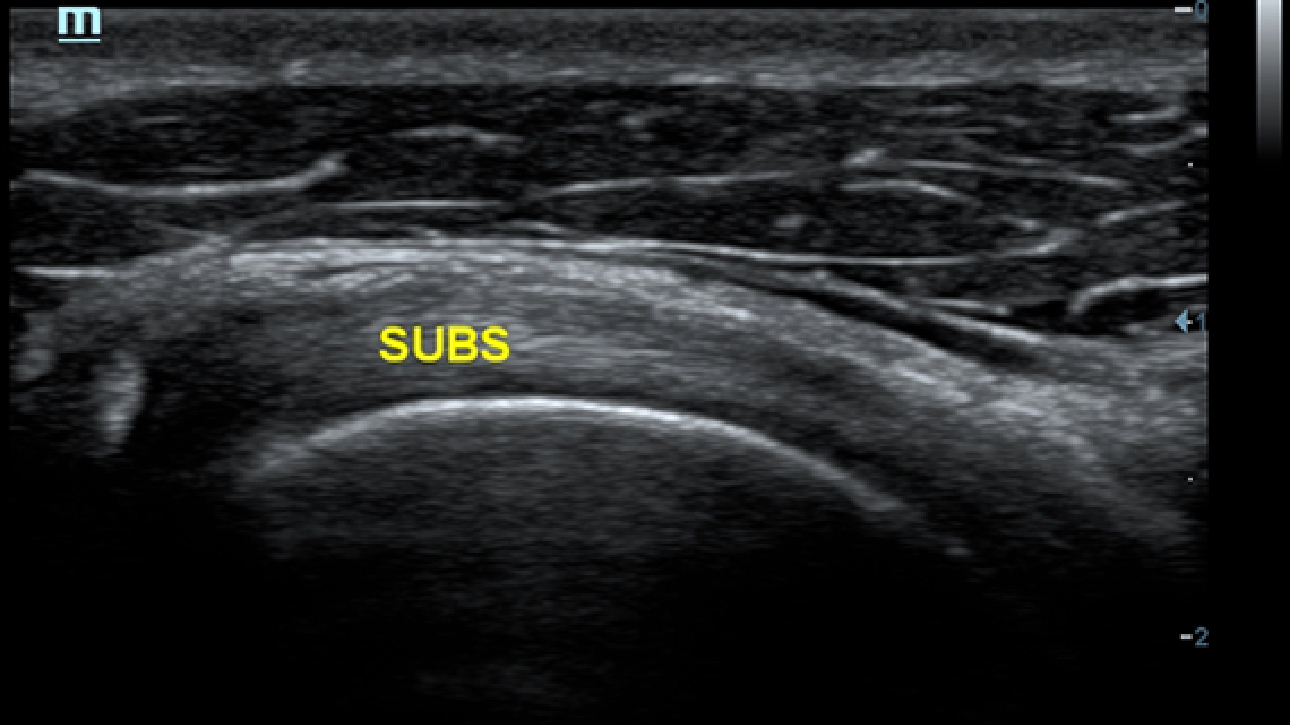

Klinische Bilder

Schallk?pfe